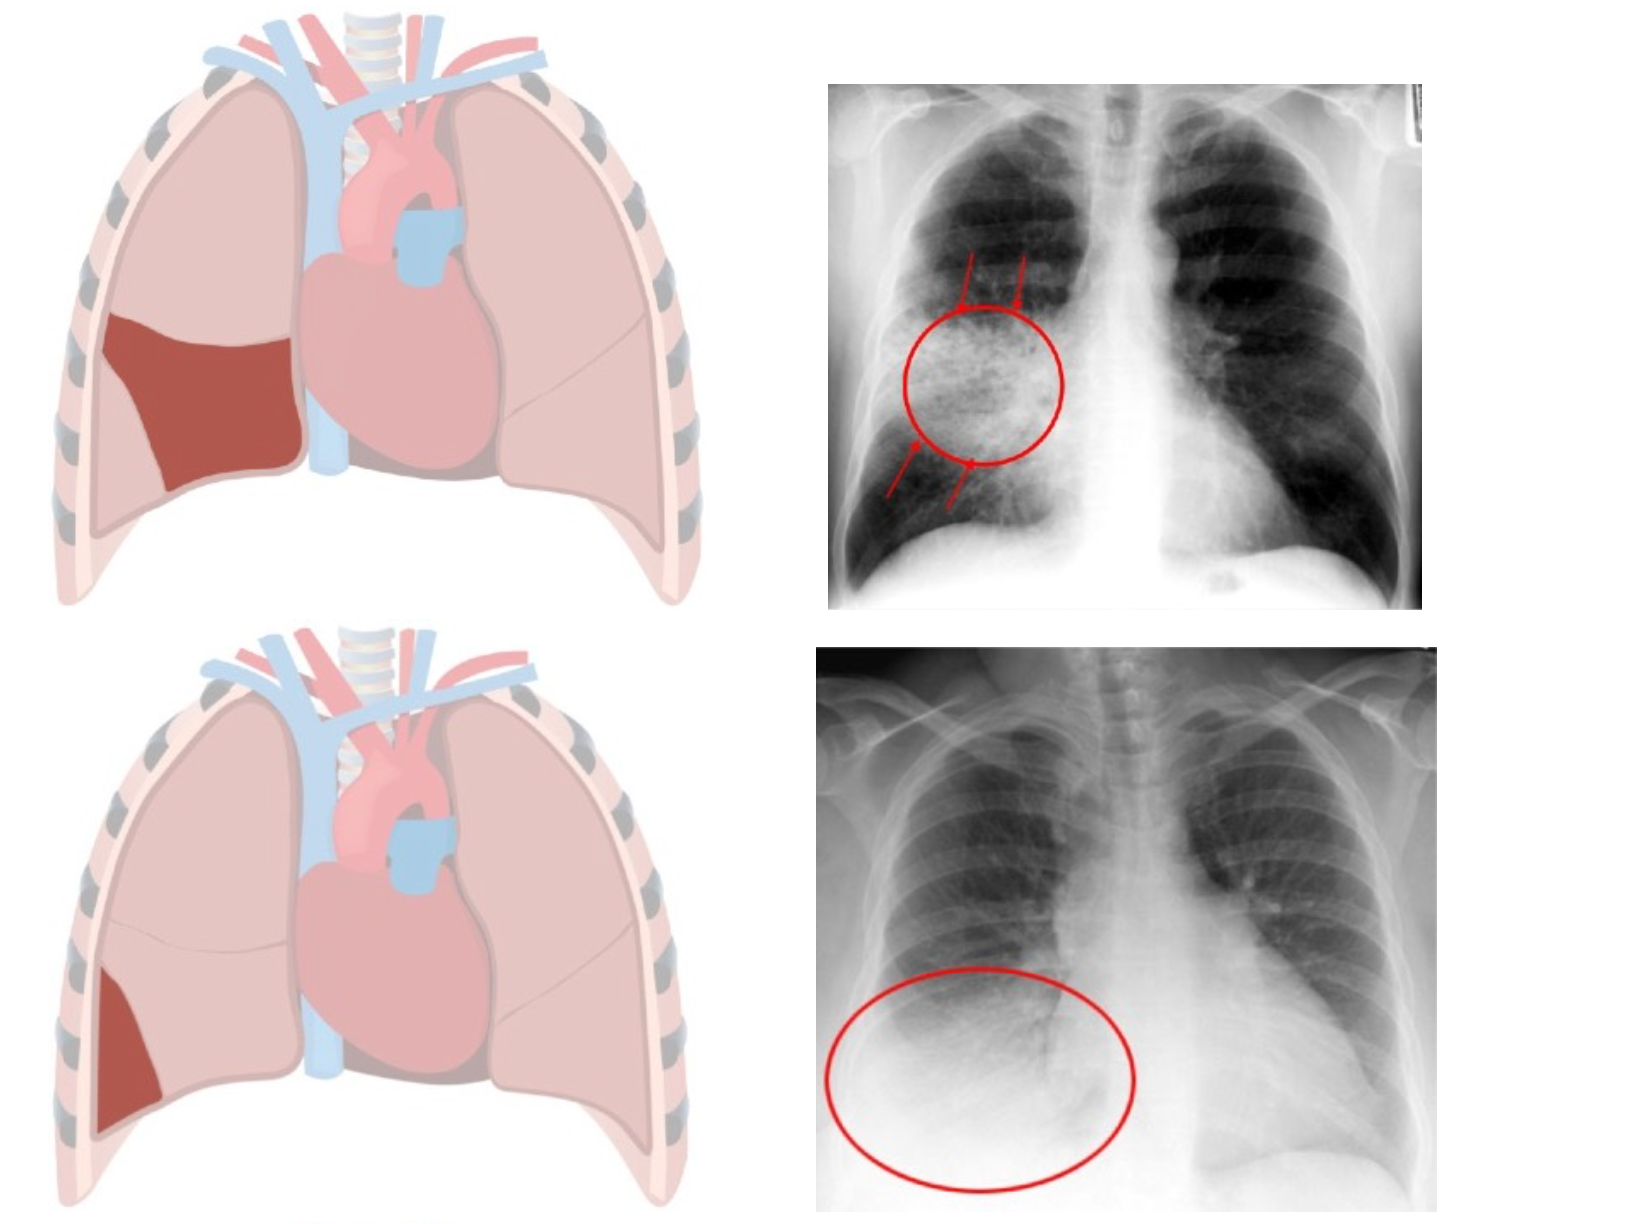

Chest x-ray helps to diagnose lobar pneumonia. The x-ray will show the pus and other substances in the affected lung lobe, which has a cloudy white appearance on the x- ray. Here are some examples of chest x-rays showing infection in different lobes: